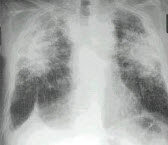

13、单项选择题

男,52岁,从事矿井工作32年,近几年出现气喘,呼吸困难,胸片如图,其最可能的诊断为()

A.双肺浸润性结核

B.双肺真菌感染

C.两肺弥漫性间质性肺炎

D.两肺弥漫性纤维化

E.矽肺